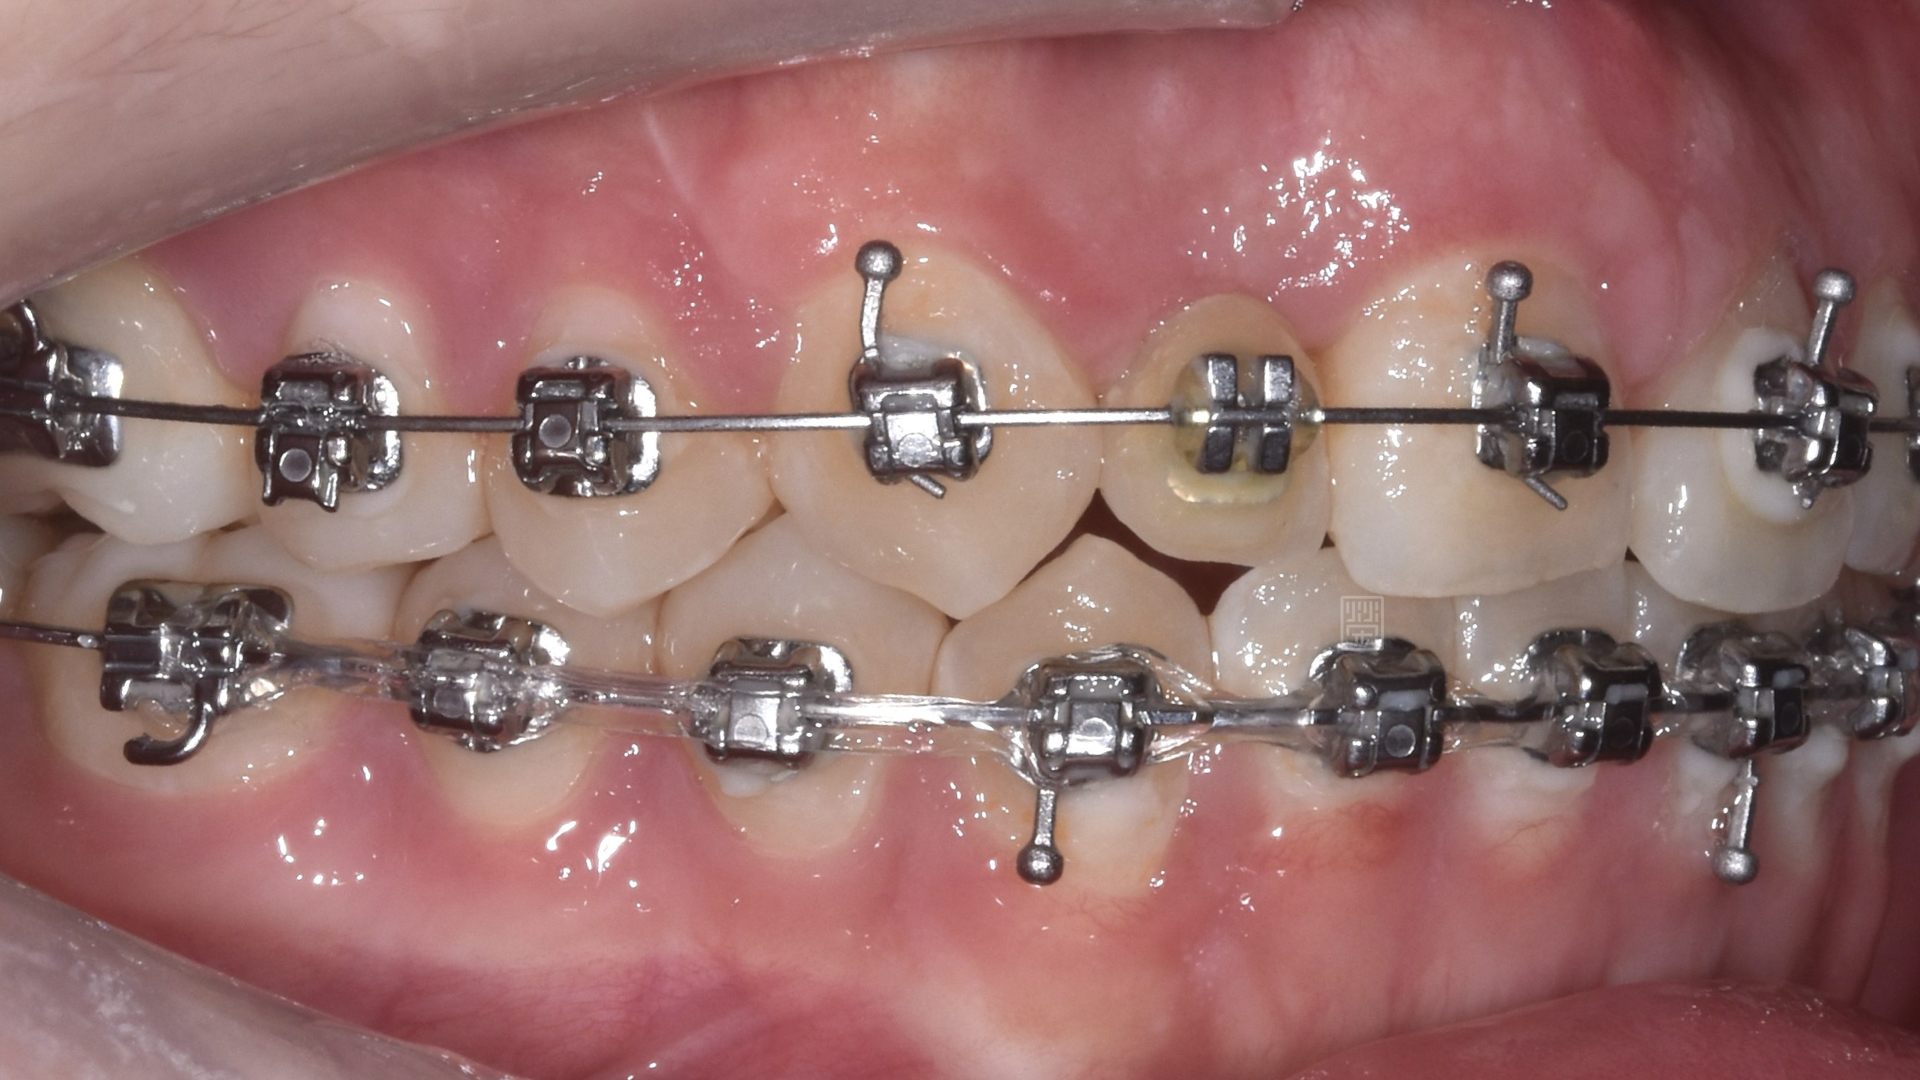

矯正移出側門牙空間

皮質骨切開手術增加牙齒移動

矯正時因牙齒沾黏骨頭無法移動